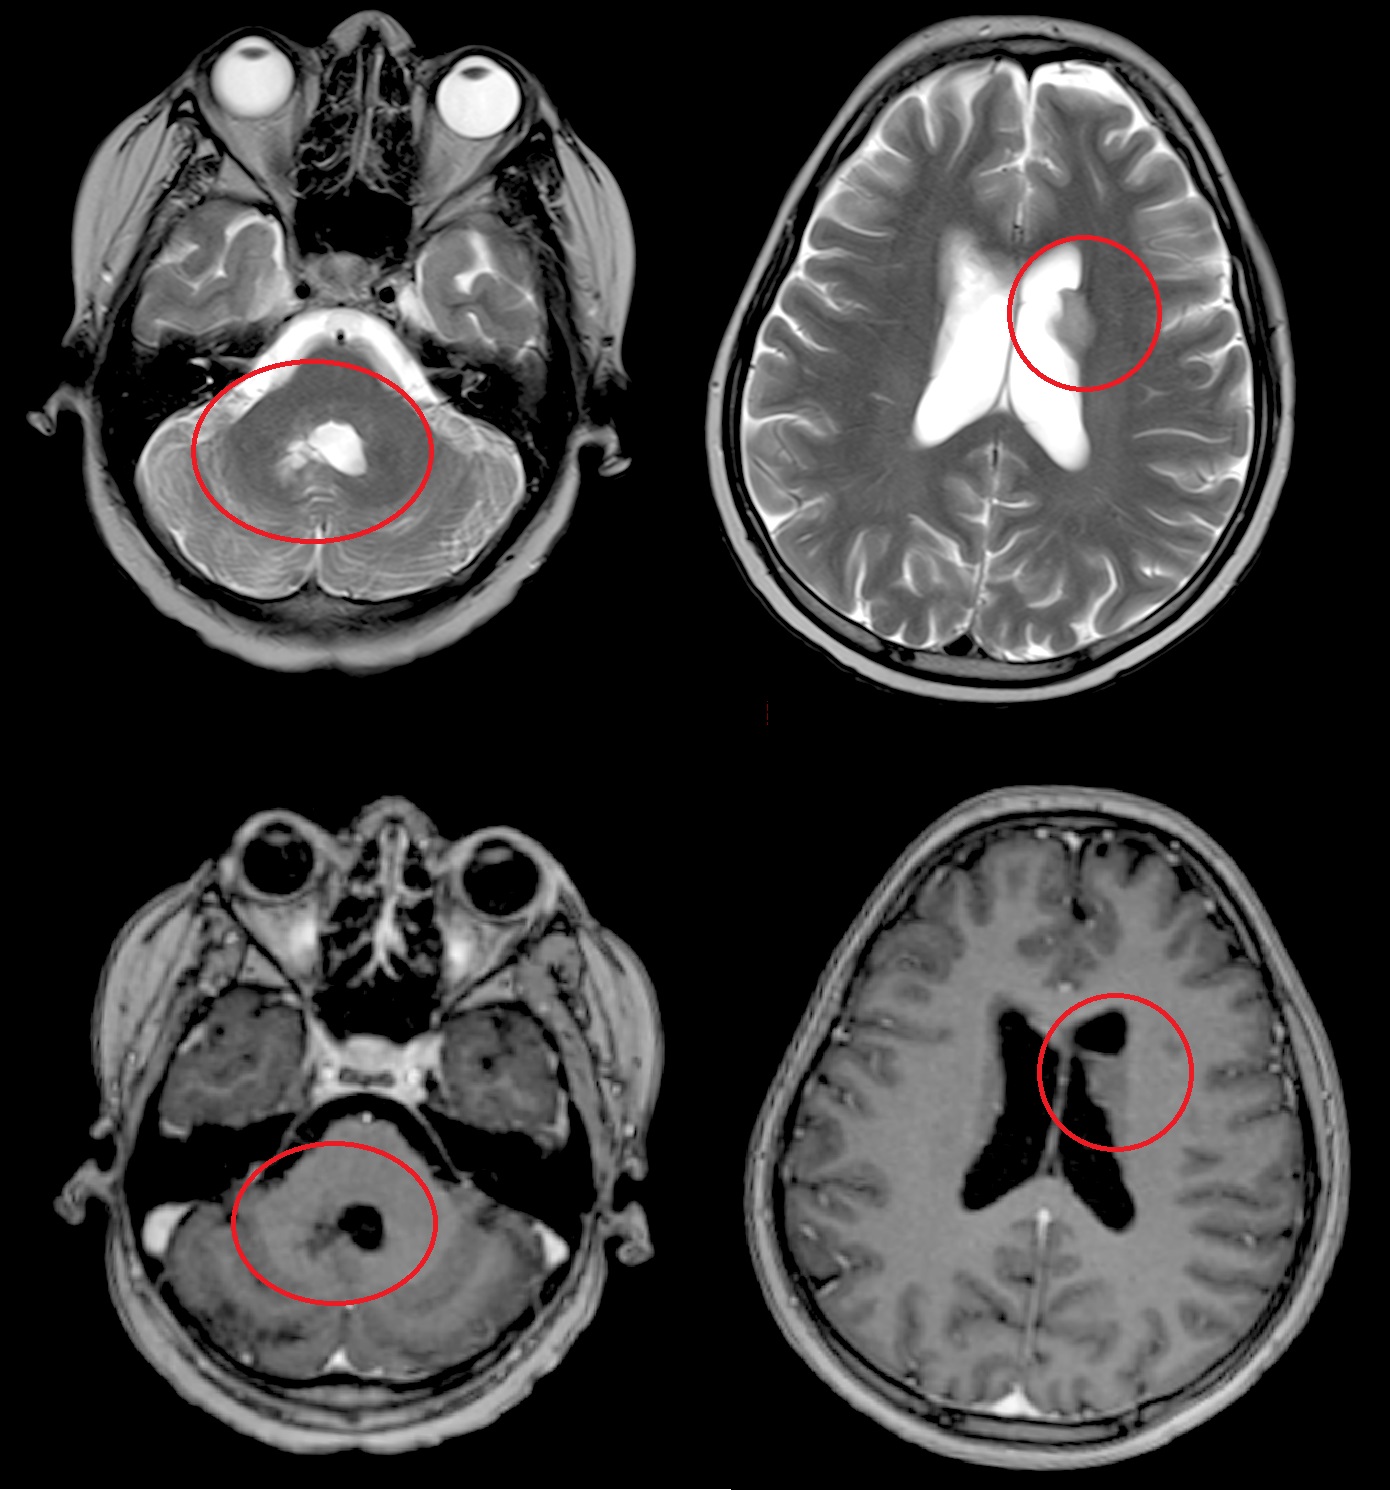

Результаты. У 19 пациентов (50 % от 38 прошедших биопсию) по данным иммуногистохимического анализа послеоперационного материала была выявлена мутация К27М в гене H3F3A. У 6 (15 %) пациентов из 38 МРТ в сроки от 2 до 5 мес (медиана – 4,5 мес) после окончания лучевой терапии выявлено нехарактерное прогрессирование ДСГ в виде метастазирования по желудочковой системе головного мозга. У остальных пациентов когорты исследования, не проходивших процедуру биопсии, подобный характер прогрессирования не наблюдался (p<0,002): у них, как правило, отмечался продолженный рост опухоли (n=96), у 4 больных диагностировано лептоменингеальное метастазирование по спинному мозгу.

Заключение. Нами выявлены случаи нетипичного прогрессирования ДСГ в виде метастазирования по желудочковой системе у детей после открытой биопсии опухоли. Есть основания полагать, что биопсия могла способствовать диссеминации ДСГ по ликворным пространствам. Необходим поиск альтернативных методов оценки молекулярно-генетических характеристик ДСГ.